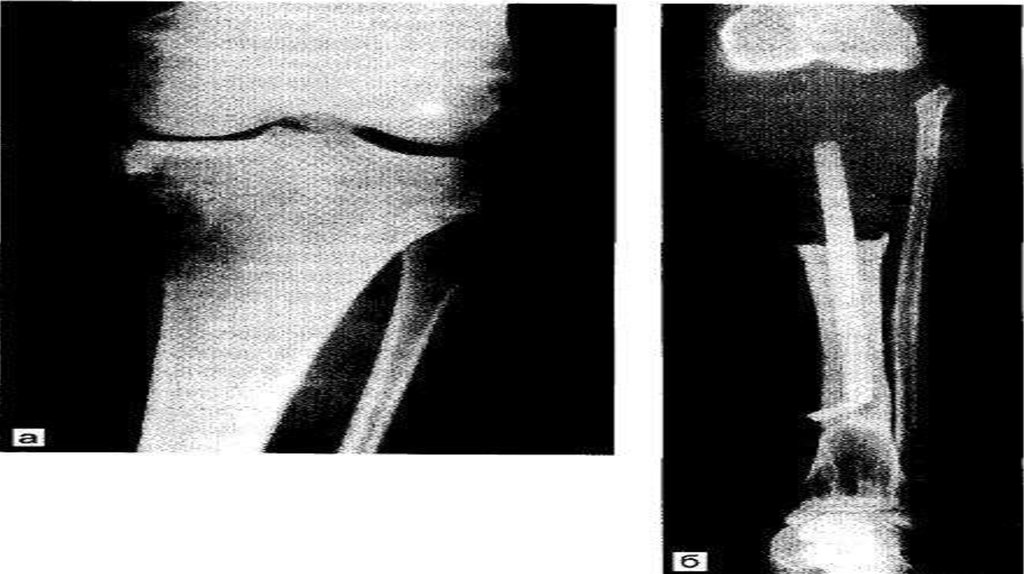

Остеолитическая

остеогенная

саркома проявляется деструктивным

очагом в кости в виде просветления

неправильной формы с нечёткими

контурами.